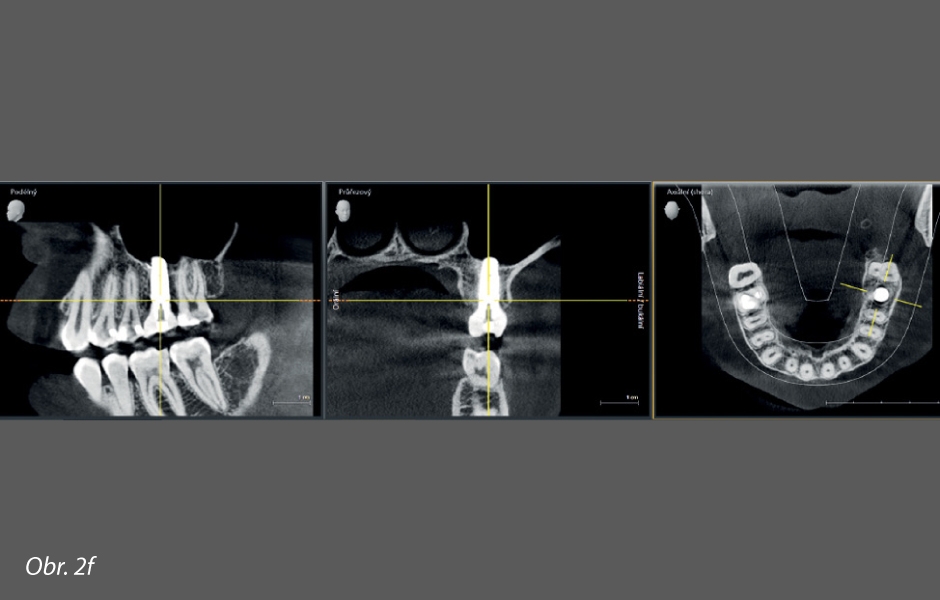

Pacientce byl 3. 5. 2018 extrahován zub 26 z důvodu přetrvávajících píštělí po neúspěšné endodontické terapii. Po extrakci jsme objevili velkou via falsa ve furkaci kořene. Zub byl očištěn, zbaven všech granulací a umělých materiálů a zpracován na autologní dentin. Hodinu po extrakci jsme vyplnili extrakční lůžko autologním dentinem (obr. 2a). Augmentát jsme zajistili křížovým stehem a ponechali bez krytí. Už za měsíc (20. 6. 2018) jsme provedli časnou flapless implantaci implantátu Biomet 3i průměru 5 mm a délky 11,5 mm se zaváděcím momentem 20 Ncm (obr. 2b). Zároveň jsme odebrali tkáň na histologickou analýzu. Preparát byl obarven barvivem Masson-Goldner trichrome, a nalezli jsme v něm velmi hustou, ještě neorganizovanou, trámčitou kost, bohatě zásobenou cévami (obr. 2c). Za 4 měsíce po implantaci (obr. 2d) byla odevzdána definitivní korunka. I s dvouletým odstupem je implantát perfektně integrován, kost stabilní a náhrada korunky funkční (obr. 2e, 2f).